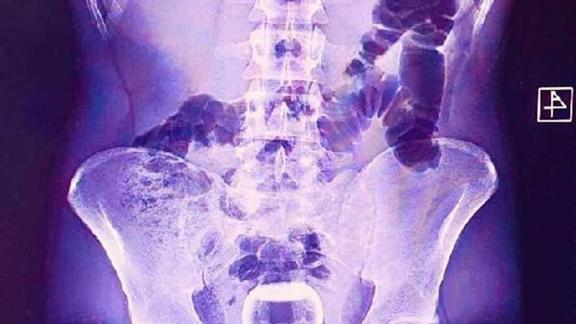

NTV'den aktarılan habere göre, acil serviste çekilen röntgende, hastanın anüs bölgesinde çay bardağı görüldü.